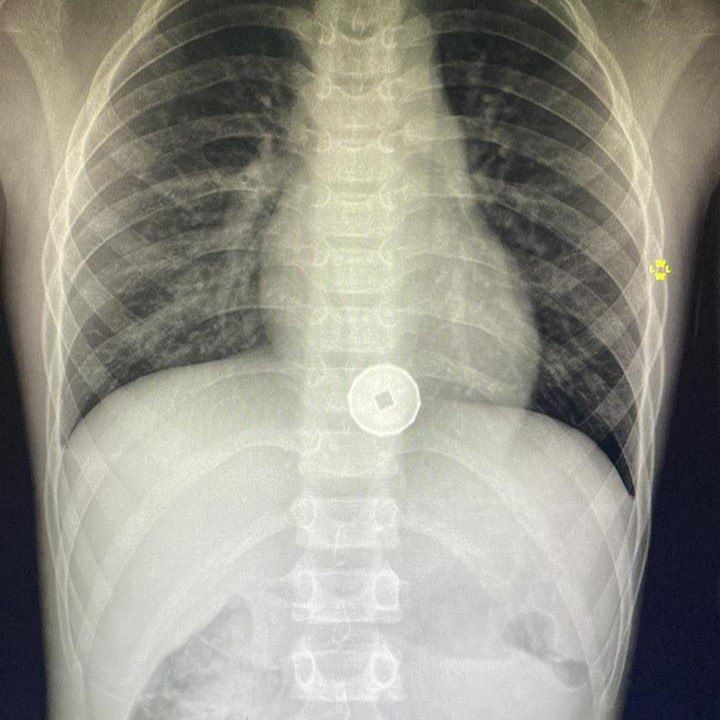

Томские врачи извлекли монету из пищевода ребенка

Врачи томской больницы скорой медицинской помощи №2 достали из пищевода восьмилетнего мальчика пластиковую монету с металлическим напылением.

Как уточняют в пресс-службе регионального департамента здравоохранения, ребенок поступил с жалобами на рвоту, болями за грудиной и нарушением функции глотания. В пищеводе мальчика был обнаружен инородный предмет. Чтобы извлечь его пришлось провести фиброэзофагогастроскопию.

Главный врач БСМП №2 Андрей Караваев подчеркнул, что ребенок может проглотить подобный предмет и до недели ощущать минимальный дискомфорт, о котором даже не сообщит взрослым. Но впоследствии это может привести к плачевному исходу. Вовремя не извлечённый инородный предмет может привести к пролежням пищевода, перфорации его стенок. Дальнейшие осложнения опасны для жизни ребенка.

В пресс-службе уточняют, что в больнице это уже второй подобный случай за месяц.